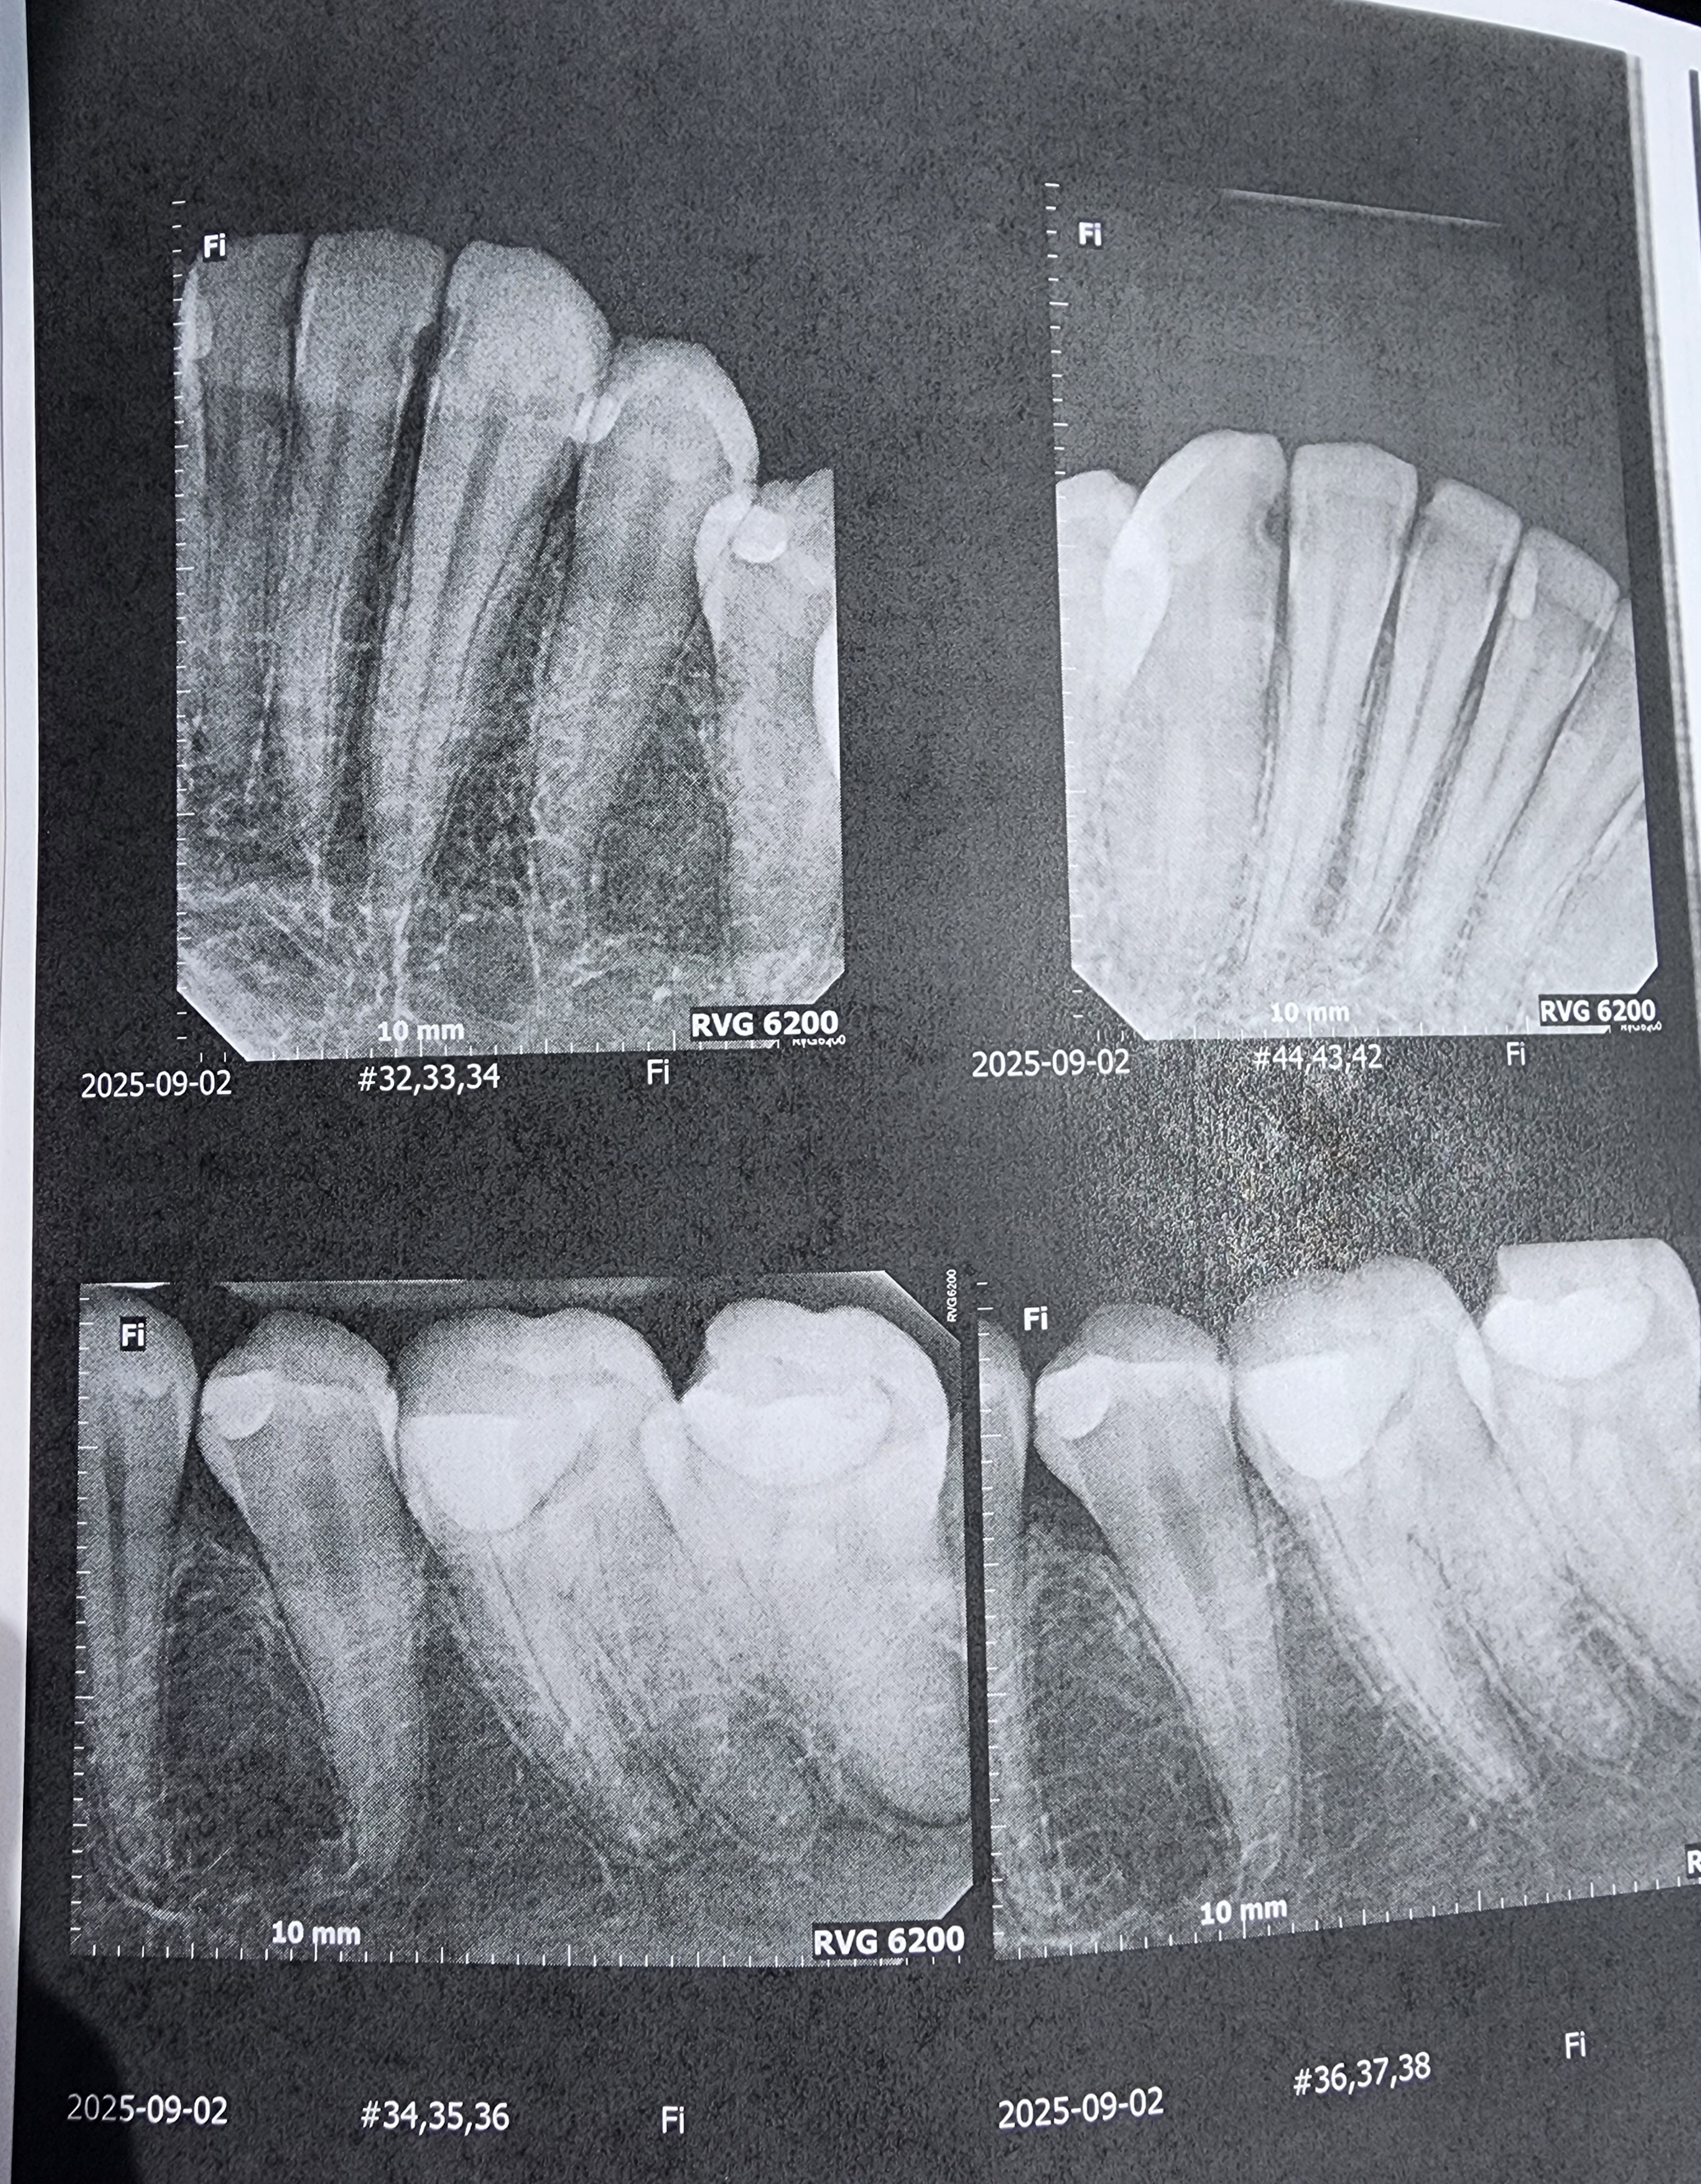

Hello. My name is Ash and those x-rays are of my not so good teeth. I knew that they weren't that good but they were worse than I could ever have imagined.

Due to an old dentist seemingly giving me bad fillings before leaving the practice, it seems I need 4 Crowns, 1 or 2 Root Canals, and a whole ton of fillings. I was prepared for a couple thousand but it seems they want about 12,400 in total. And this includes a dental plan card they let me sign up for to half the entire bill. They want me to pay before each appointment and at this point I dont know what I can do.